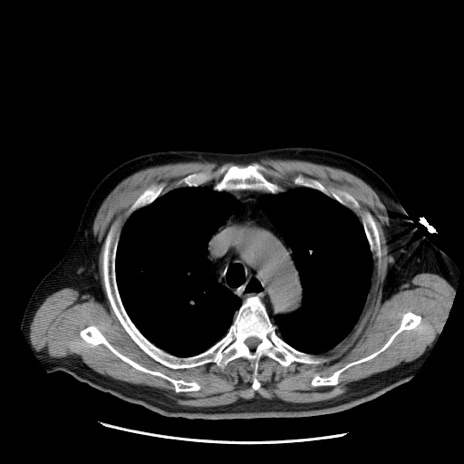

症例20(横断像)

【症例】 60歳代男性

【主訴】 腹部膨満、嘔吐

【現病歴】5日前頃より倦怠感を認め食事量減少し4日前の朝嘔吐、食事摂取困難となった。 3日前近医受診し点滴施行され整腸剤などを処方された。 当日他院を受診し、腹部膨満著明、炎症反応の上昇(CRP10.8、WBC11200)あり、紹介受診となる。

【身体所見】 意識JCS1 受け答えがはっきりしないBP 111/57mHg、 P 67bpm、、BT35.2°C、SpO2 97%(RA)、 腹部:膨隆、打診で鼓音あり、全体的に圧痛有り、腸蠕動音(-)、反跳痛ははっきりせず。

【データ】WBC 11400、CRP 14.20